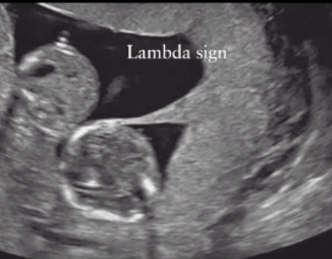

what is the lambda sign indicative of

2 placentas - DCDA twins